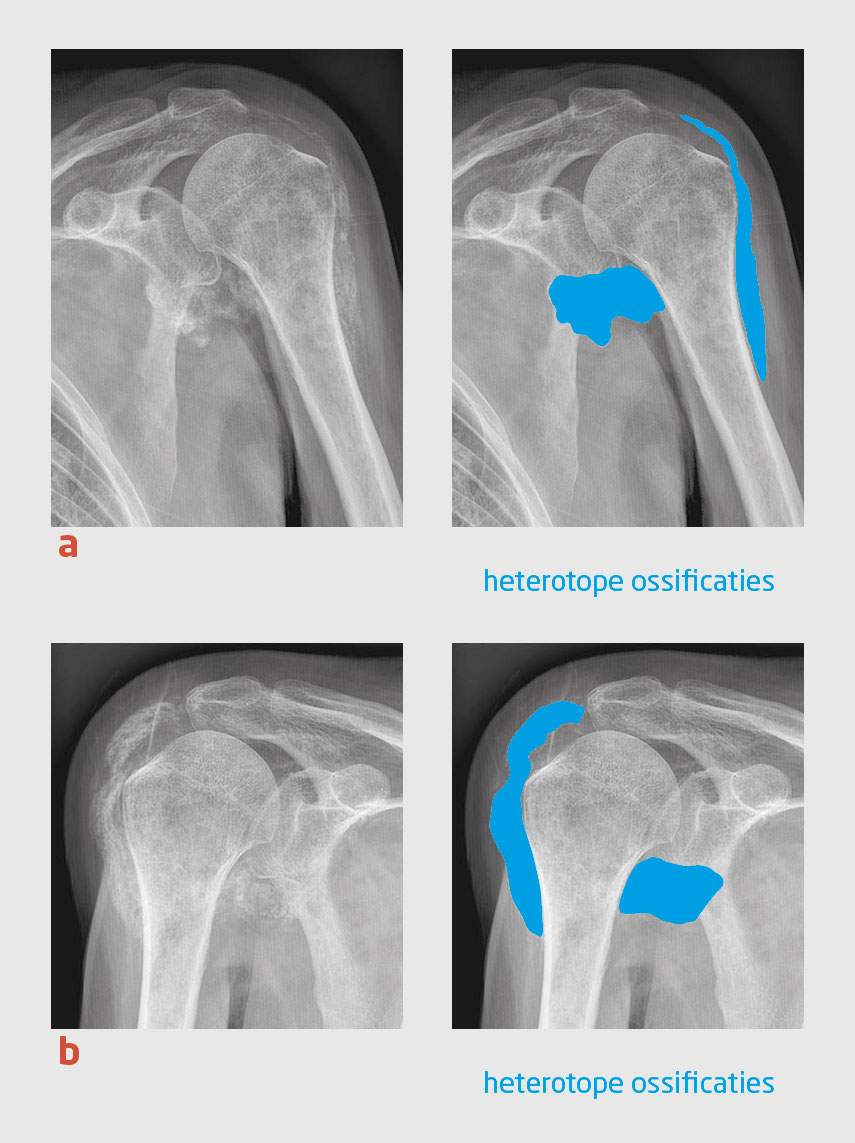

Figuur 1

Heterotope ossificaties rondom beide glenohumerale gewrichten van patiënt A.

Figuur 1 | Heterotope ossificaties rondom beide glenohumerale gewrichten van patiënt A.

Röntgenfoto’s van (a) de linker en (b) de rechter schouder van patiënt A. Uitgebreide heterotope ossificaties zijn zichtbaar in de weke delen rondom de beide glenohumerale gewrichten.